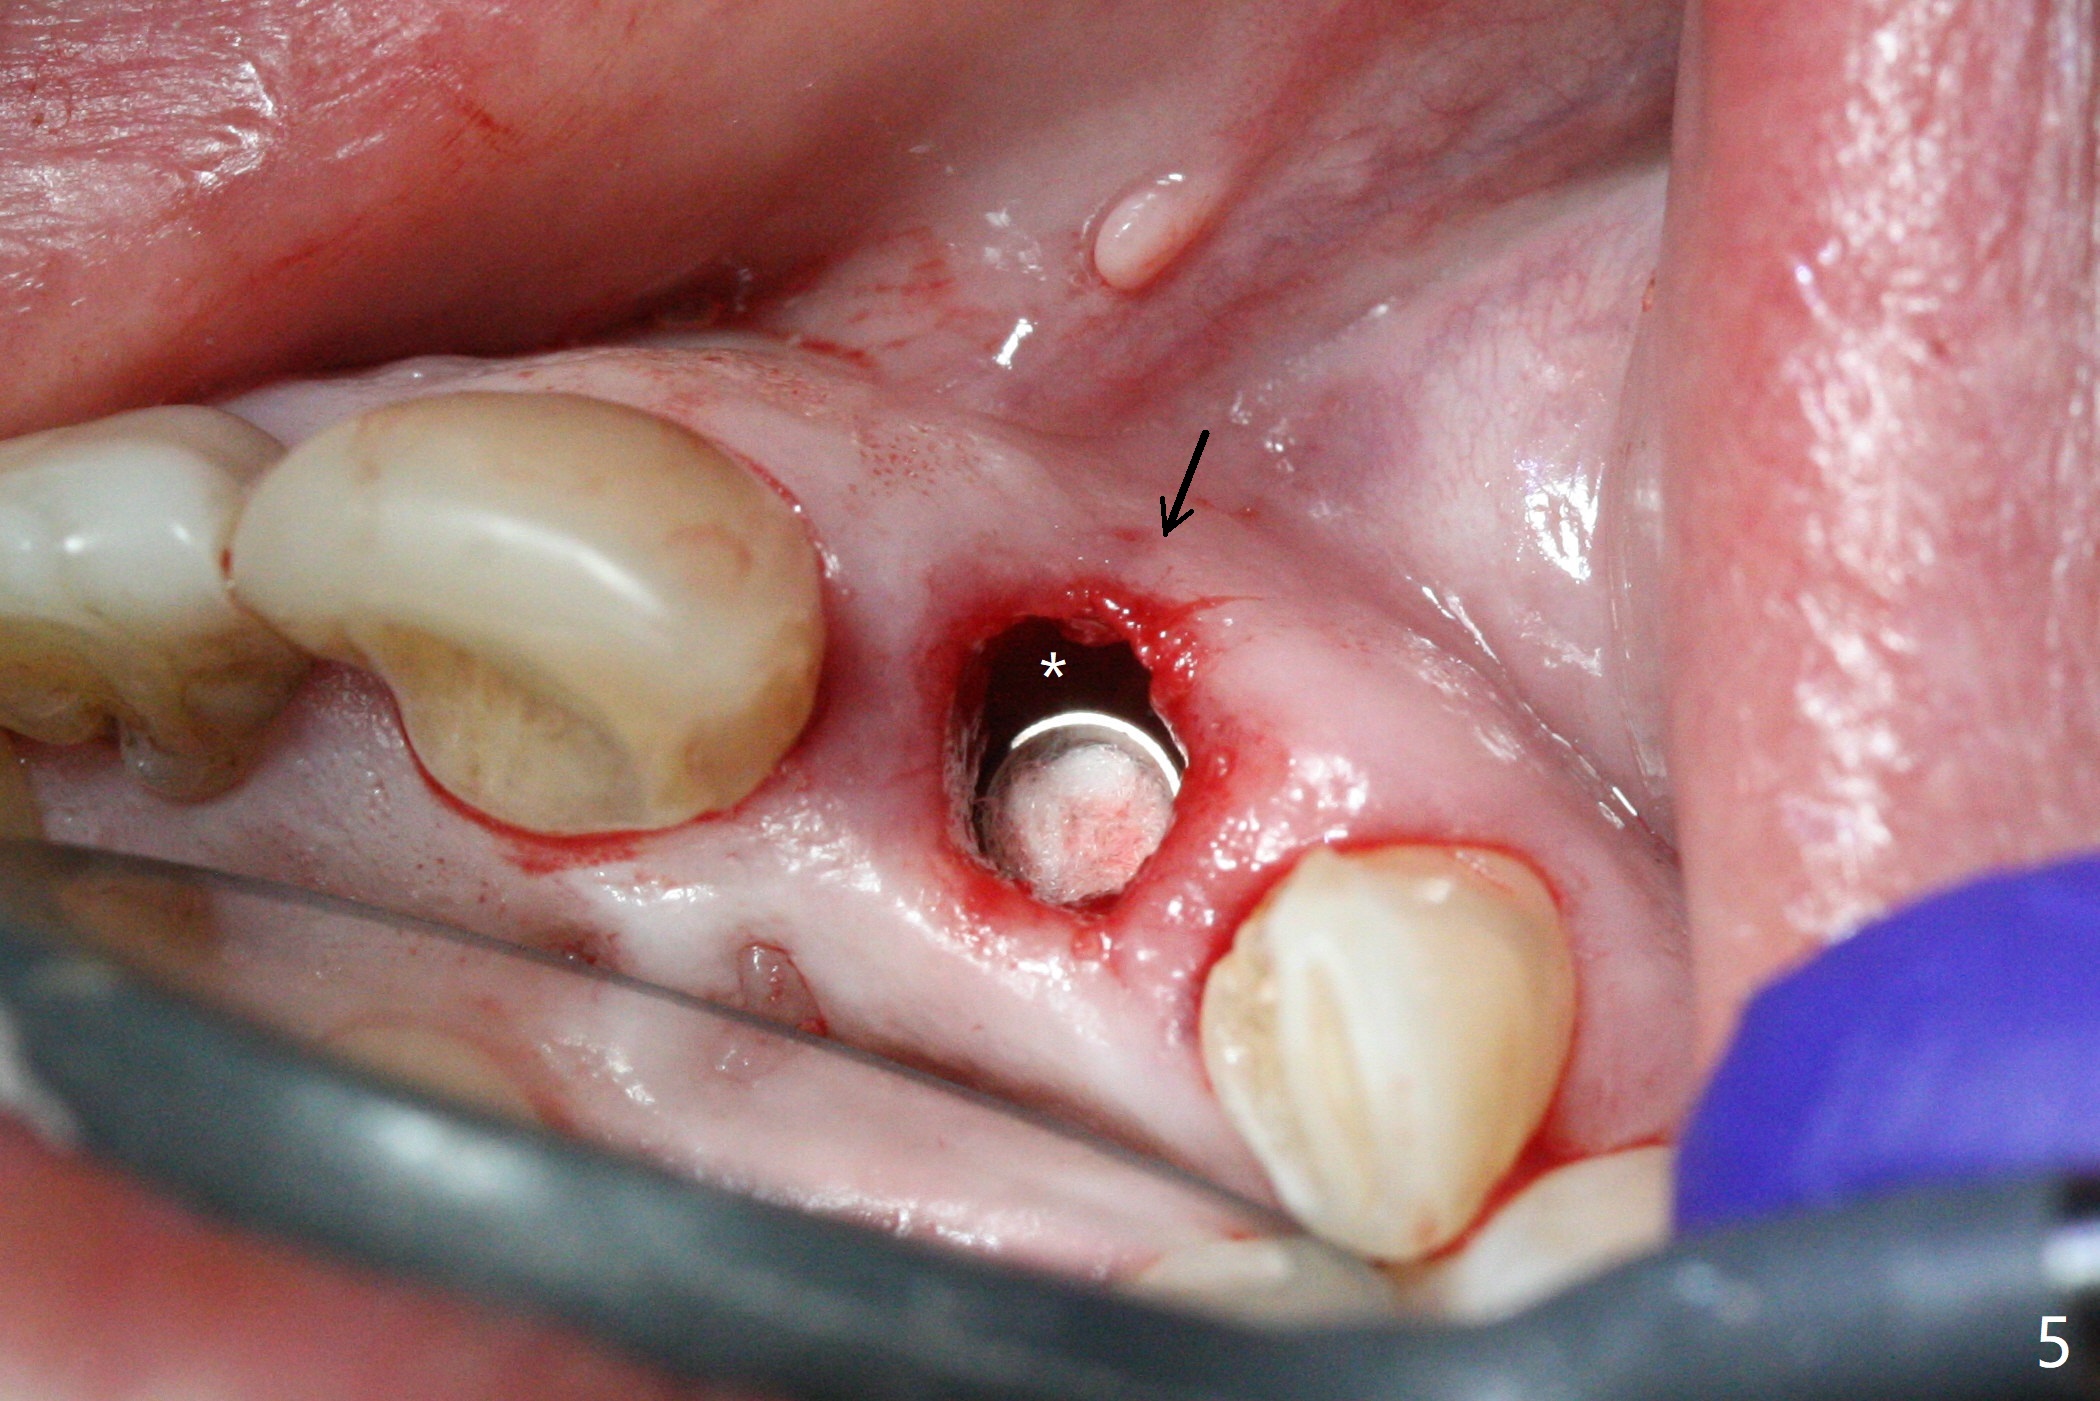

In spite of the incisobuccal shift of the tooth #9 with gingival recession (Fig.1) and loss of the buccal plate (intraop finding), there is no buccal contour collapse (Fig.2 *), due to the presence of the buccal bone of the neighboring teeth and the root of the affected tooth. After extraction, osteotomy (Fig.3) and dummy implant try in (Fig.4), a definitive implant is placed palatally with the buccal gap (Fig.5 *). In fact there is mild buccal contour collapse prior to bone graft (Fig.5 arrow). When allograft (Vera, Fig.6,7 *) is packed buccal to the implant and overlying abutment as a solid support, the buccal contour seemingly returns normal (Fig.6 arrowhead). An immediate provisional is fabricated to prevent loss of the bone graft during healing period. Bone graft kept in place by the provisional turns yellow 6 days postop (Fig.8). The buccal plate remains strong, while the fistula becomes indistinguishable. After adjustment of the provisional margin a few times (nearly 3 months postop, Fig.9,10), the gingival margin appears to have grown incisally, as compared to Fig.1. There is minimal buccal bone collapse (Fig.10). Dislodgement of the abutment and provisional forces her to return 1 year 4 months postop; the socket has healed (Fig.11). The buccal plate is not concave 1 year 4 months postop (Fig.12). The gingiva is slightly recessive (Fig.13) with mild buccal plate concavity (Fig.14) immediately before cementation. The implant could be placed ~ 1 mm deeper (Fig.15).